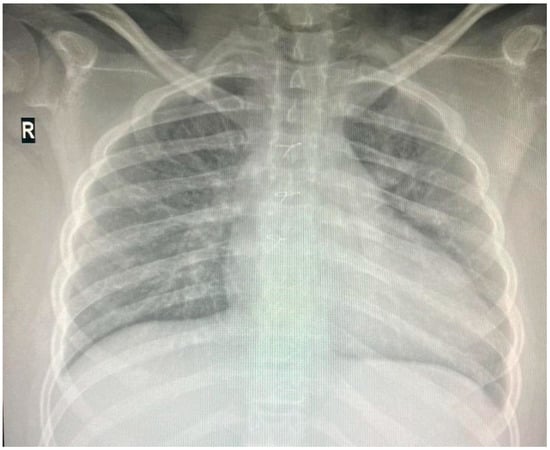

Individuals with 18q deletion syndrome present with various clinical characteristics, including cardiac anomalies. Nonetheless, genotype–phenotype correlations for cardiac anomalies in 18q deletion syndrome have rarely been reported [6] The patient was diagnosed with Tetralogy of Fallot, a congenital heart defect characterized by four anatomical abnormalities: ventricular septal defect (VSD), pulmonary stenosis, right ventricular hypertrophy, and an overriding aorta. He underwent successful corrective surgery in Germany at the age of one and has received infective endocarditis prophylaxis ever since. Since then, he has received biannual pediatric cardiology consultations at “Grigore Alexandrescu” Emergency Children’s Hospital. His latest cardiac evaluation described a grade II diastolic murmur at the left parasternal area, and the cardiac ultrasound showed no residual shunts but moderate pulmonary regurgitation. Cardio-pulmonary x-ray at the age of 14 is depicted in Figure 3.

Figure 3. Thoracic X-ray: cardiomegaly, boot-shaped heart.